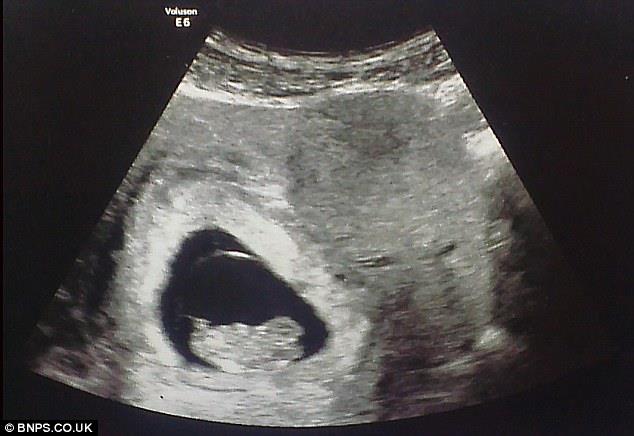

Slika sa ultrazvuka

USLIKAN: Anđeo čuvar bdi nad nerođenom bebom

LONDON - Buduća mama En Klulou ostala je zatečena kada je na slici ultrazvuka svoje nerođene bebe videla lice muškarca nalik vanzemaljskom?!

Lik nalik nekom duhu zurio je u nju sa crno-bele fotografije. Džinovska ljudska, ali izdužena glava delovala je zastrašujuće međutim trudnica se nije uplašila - ubeđena je da je to anđeo čuvar njenog nerođenog deteta.